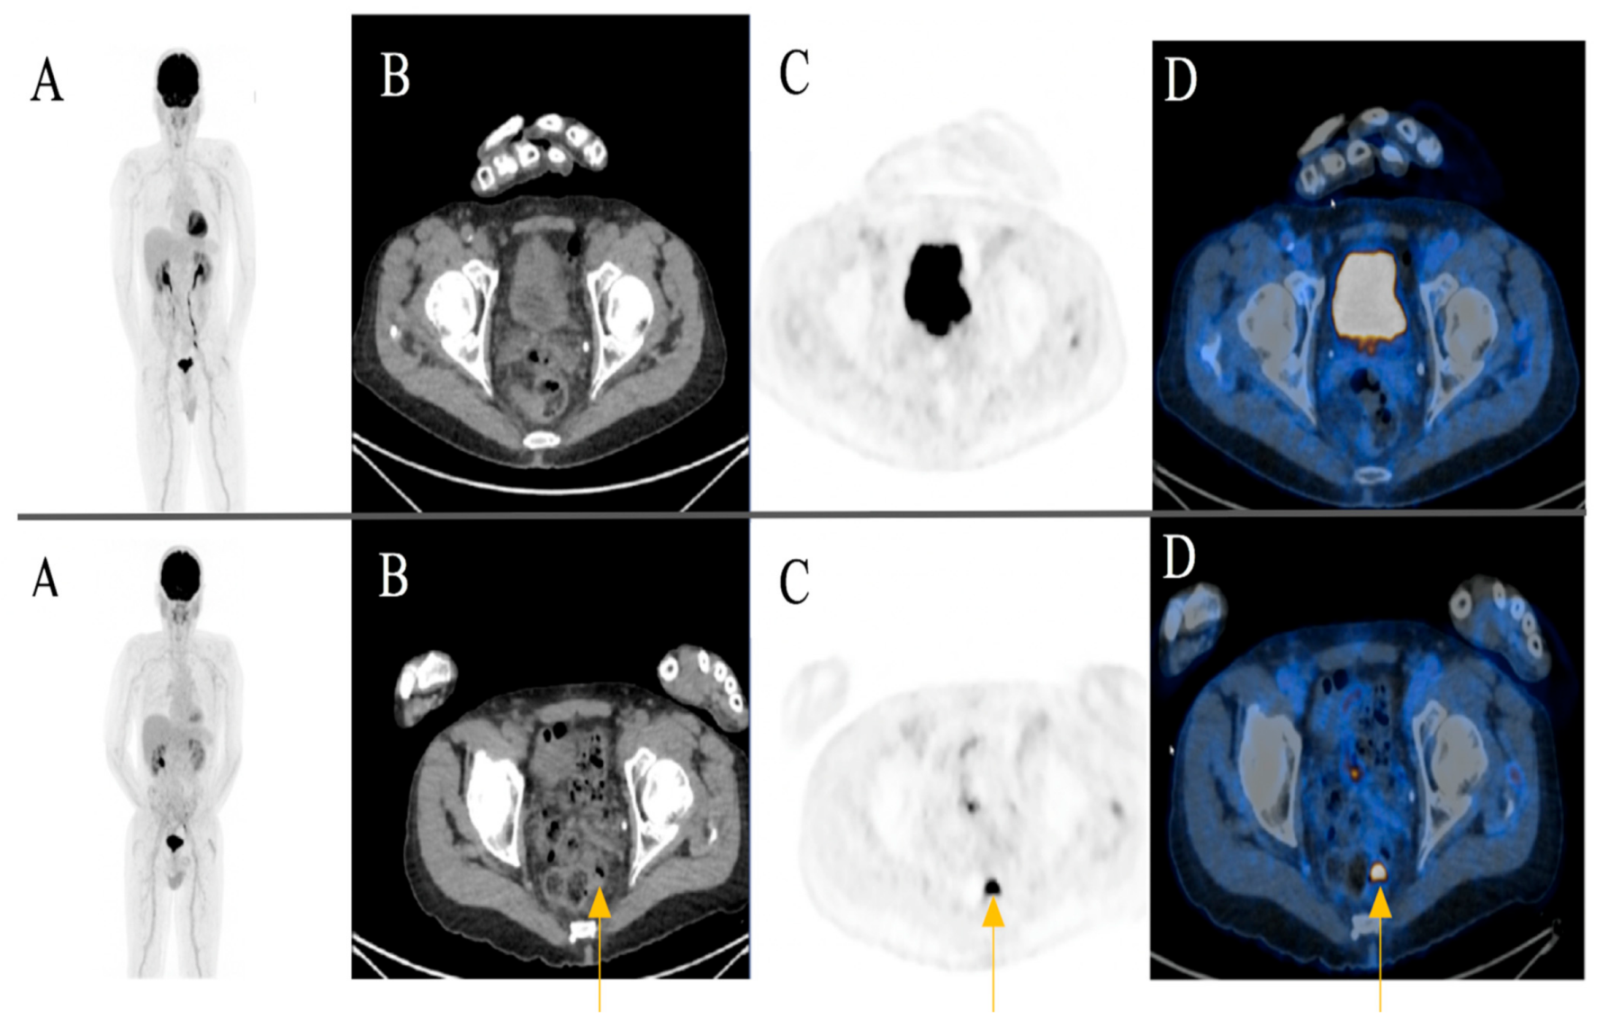

A focal FDG-uptake with wall thickening in the rectosigmoidal colon was also observed in a 72-year-old male patient with metastatic cutaneous melanoma stage IIIC during treatment response assessment. A rectoscopy was subsequently performed based on the recommendation of the reporting physicians. The biopsy revealed a well-differentiated adenocarcinoma of the colon (Figure 4) (Case 2).

Figure 4. A 72-year-old male patient initially with metastatic cutaneous melanoma stage IIIC (T0 N2b M0). (A) Maximum intensity projection (MIP); (B) Computed Tomography (CT) axial of pelvis; (C) Positron Emission Tomography (PET) axial of pelvis; (D) Fused images PET/CT axial of pelvis. First row: FDG-PET/CT performed for extended staging after left axillary lymphadenectomy without evidence of metabolically active melanoma, nodal or distant metastasis. Second row: Follow-up for treatment response assessment under anti-PD1 monotherapy. Three months after treatment initiation, a new metabolically active wall thickening of the rectosigmoidal colon was seen (yellow arrow). A rectoscopy was subsequently recommended for further evaluation. The biopsy revealed a well-differentiated adenocarcinoma of the colon.